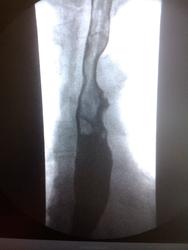

Пациентка, 74 года. Операция по поводу дивертикула пищевода лет 25 назад. Нужны мнения!

Ахалазия кардии, скользящая грыжа пищеводного отверстия диафрагмы, мелкий дивертикул с/3 пищевода - это мнение.

Тракционный дивертикул пищевода. ГПОД. Эзофагоспазм. За ахалазию сомнительно. А вот почему пищевод такой широкий - стоит задуматься.

Может быть он гипотоничный + третичные сокращения вот и выглядит широким, возможно там и эзофагит.

Я такие широкие пищеводы вижу регулярно при склеродермии, например. И клиницисты как бы должны знать о ее существовании, например же. Наше дело - констатировать факты, а их интерпритацию стоит все же оставить другим докторам.

"Нужны мнения!" Мнение: плохо оперировали тогда или: не причину, а следствие. Дивертикул есть и лит есть. ИМХО. А где причина - коллеги по поводу дистального отдела отд. пищевода  уже писали. Теоретически - проблема с 12п. кишкой( по Витебскому)